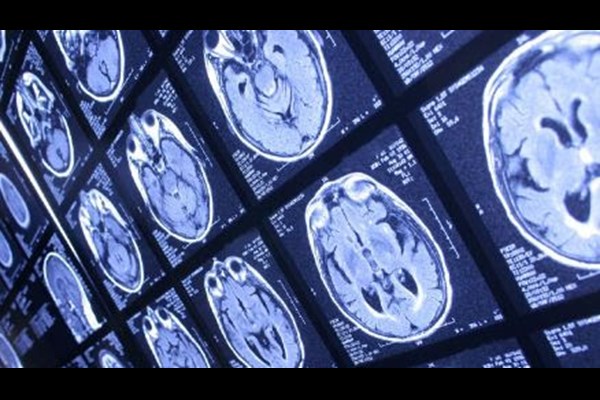

متخصصان استرالیایی و بین‌المللی می‌گویند پیاده‌روی ۵۰۰۰ تا ۷۵۰۰ قدم در روز می‌تواند به کند کردن تغییرات مغزی مرتبط با بیماری آلزایمر کمک کند.

سبک زندگی- رمزگشانیوز؛ ایسنا به نقل از شینهوا نوشت: این مطالعه که در مجله Nature Medicine منتشر شده است، ۲۹۴ بزرگسال ۵۰ تا ۹۰ ساله با عملکرد طبیعی مغز را تا ۱۴ سال پیگیری کرده و تعداد گام‌های روزانه، عملکرد مغز و تجمع پروتئین‌های مرتبط با آلزایمر نظیر «تائو» در مغز آنها را زیر نظر داشته است.

در این مطالعه آمده است که افزایش فعالیت بدنی با کاهش سرعت زوال عملکرد مغز مرتبط است که به نوبه خود با تجمع کندتر پروتئین‌های مرتبط با آلزایمر در مغز ارتباط دارد.

متخصصان دانشگاه ملبورن استرالیا، دانشگاه ماساچوست جنرال بریگام وابسته به دانشکده پزشکی هاروارد در ایالات متحده و همچنین دانشگاه تورنتو در کانادا گفتند: کسانی که علائم اولیه آلزایمر را در مغز خود نشان می‌دهند، ممکن است بتوانند با ورزش روزانه در حد متوسط، روند پیشرفت آن را کُند کنند.

طبق این مطالعه، شرکت‌کنندگانی که بیش از ۵۰۰۰ قدم در روز برمی‌داشتند، کاهش کندتری در حافظه و تفکر نشان دادند که با کاهش تجمع تائو، پروتئینی مرتبط با پیشرفت آلزایمر، مرتبط بود.

متخصصان گفتند که تجمع تائو و زوال شناختی در سطح فعالیت متوسط ۵۰۰۱ تا ۷۵۰۰ قدم در روز ثابت ماند و افزودند که حتی فعالیت متوسط، حدود ۳۰۰۰ تا ۵۰۰۰ قدم با کاهش قابل توجه تجمع تائو و زوال شناختی مرتبط است.